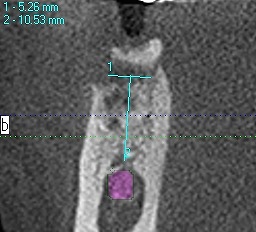

抜歯即時で行うと大穴が開いている状況なので、基準となる骨の位置が分かりにくいです

最初のラウンドドリリングのラウンドバーにて下顎管の距離を測る

CTを取ります

距離がないことがわかります

わずか1mm、2mmの世界の勝負なためいつもいい緊張感

にて行っています